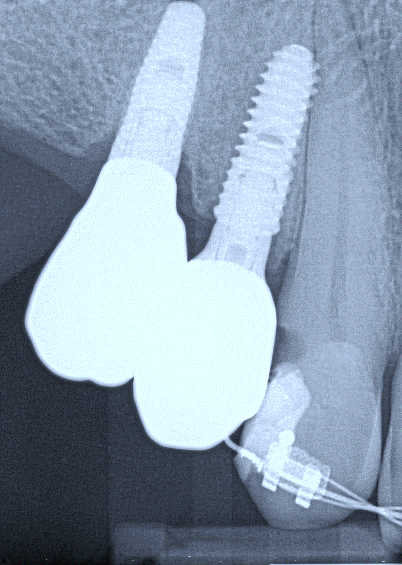

16. (Select ONE OR MORE correct answers.)

Tooth 1.8 is planned for surgical extraction. Which radiographic findings suggest an increase in the degree of difficulty of the extraction?